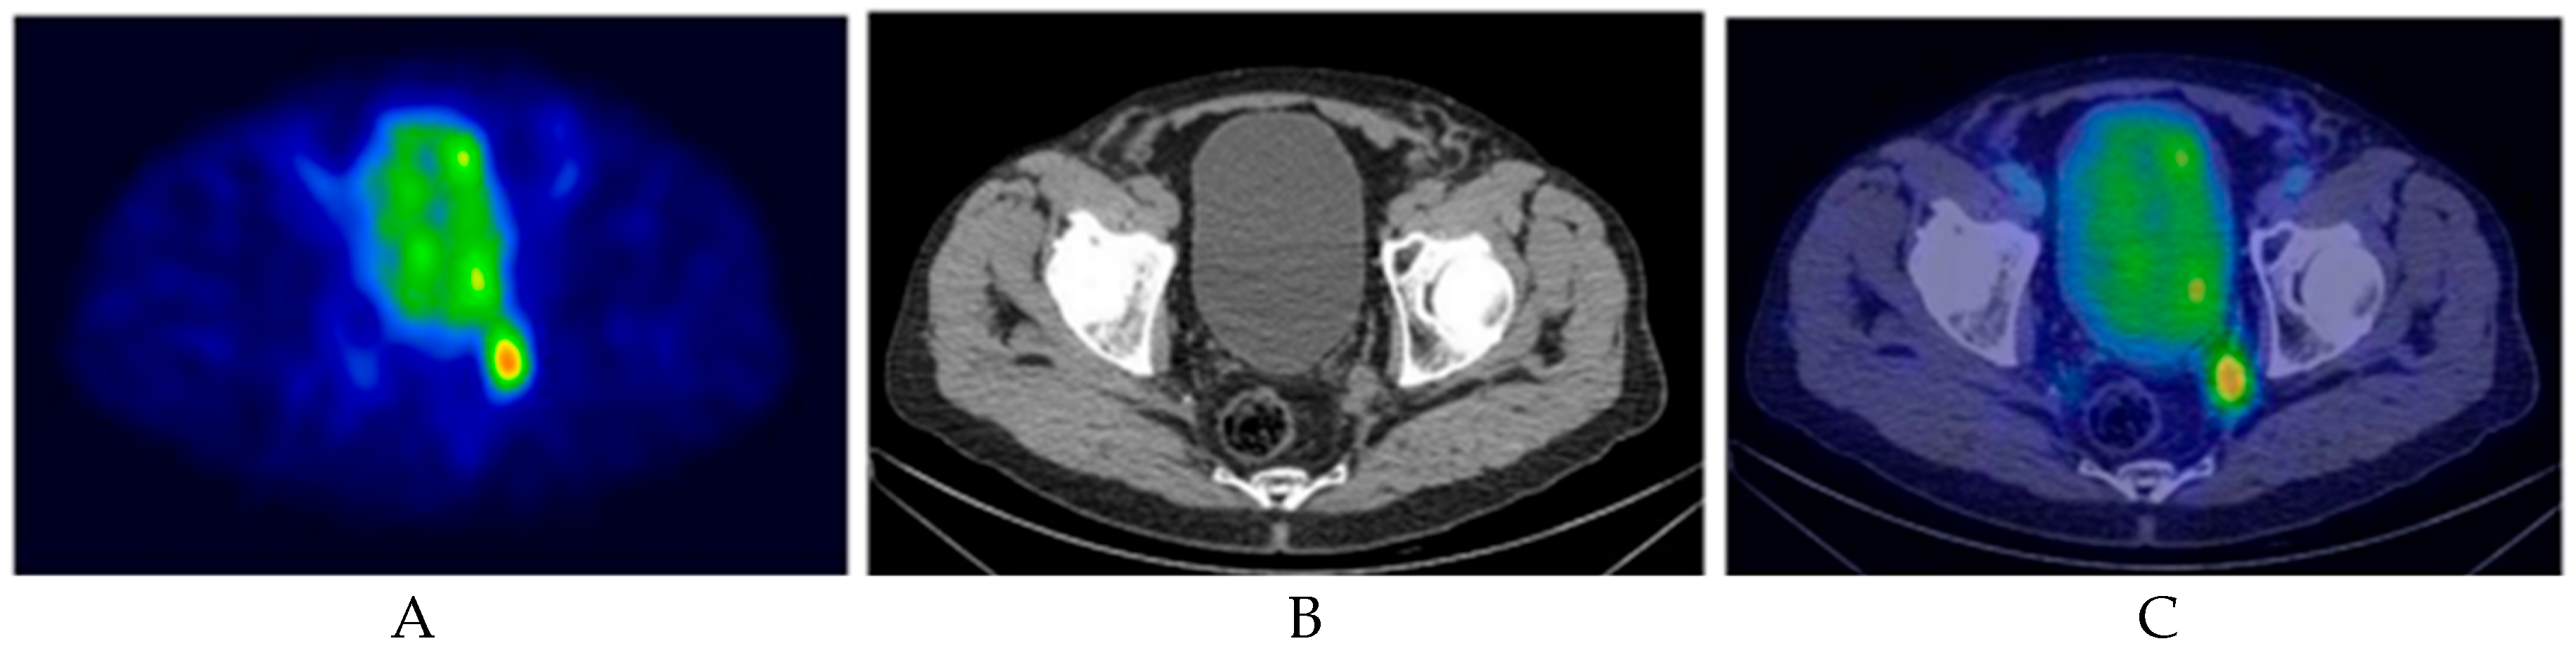

5.2. PSMA-RGS

5.2.1. Recurrent Prostate Cancer Setting

- Quarta, L.; Stabile, A.; Chiti, A.; Montorsi, F.; Briganti, A.; Gandaglia, G. Radioguided Surgery for Prostate Cancer. Eur. Urol. Focus 2025, 11, 29–32. [Google Scholar] [CrossRef]

- Quarta, L.; Mazzone, E.; Cannoletta, D.; Stabile, A.; Scuderi, S.; Barletta, F.; Cucchiara, V.; Nocera, L.; Pellegrino, A.; Robesti, D.; et al. Defining the optimal target-to-background ratio to identify positive lymph nodes in prostate cancer patients undergoing robot-assisted [Tc]Tc-PSMA radioguided surgery: Updated results and ad interim analyses of a prospective phase II study. Eur. J. Nucl. Med. Mol. Imaging 2024, 51, 3789–3798. [Google Scholar] [CrossRef]

- de Barros, H.A.; van Oosterom, M.N.; Donswijk, M.L.; Hendrikx, J.J.; Vis, A.N.; Maurer, T.; van Leeuwen, F.W.; van der Poel, H.G.; van Leeuwen, P.J. Robot-assisted Prostate-specific Membrane Antigen-radioguided Salvage Surgery in Recurrent Prostate Cancer Using a DROP-IN Gamma Probe: The First Prospective Feasibility Study. Eur. Urol. 2022, 82, 97–105. [Google Scholar] [CrossRef] [PubMed]

- Berrens, A.-C.; Sorbi, M.A.; Donswijk, M.L.; de Barros, H.A.; Azargoshasb, S.; van Oosterom, M.N.; Rietbergen, D.D.; Bekers, E.M.; van der Poel, H.G.; van Leeuwen, F.W.; et al. Strong Correlation Between SUV on PSMA PET/CT and Numeric Drop-In γ-Probe Signal for Intraoperative Identification of Prostate Cancer Lesions. J. Nucl. Med. 2024, 65, 548–554. [Google Scholar] [CrossRef]